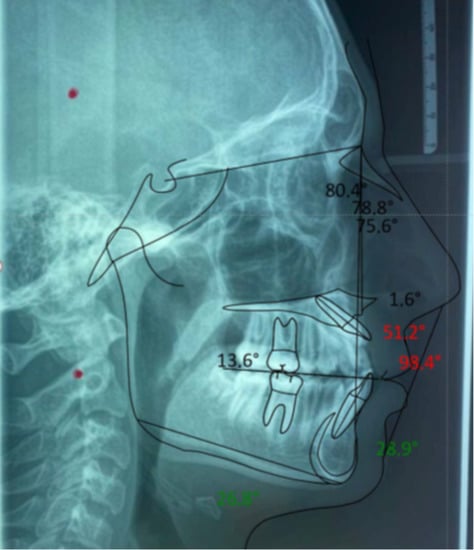

- Latero-Lateral Teleradiography (LLT) of the head with cephalometric trace to assess the height and inclination of the crown and root of the impacted tooth.

| Values | Normal | |

|---|---|---|

| SNA | 80.4° | 82°+/−2° |

| SNB | 78.8° | 80°+/−2° |

| ANB | 1.6° | 2°+/−2° |

| GONIAC ANGLE | 116.1° | 130°+/−7° |

| INTERINCISIVE ANGLE | 98.4° | 131°+/−6° |

| SUPERIOR INCISOR ANGLE | 51.2° | 22°+/−2° |

| INFERIOR INCISOR ANGLE | 28.9° | 25°+/−2° |